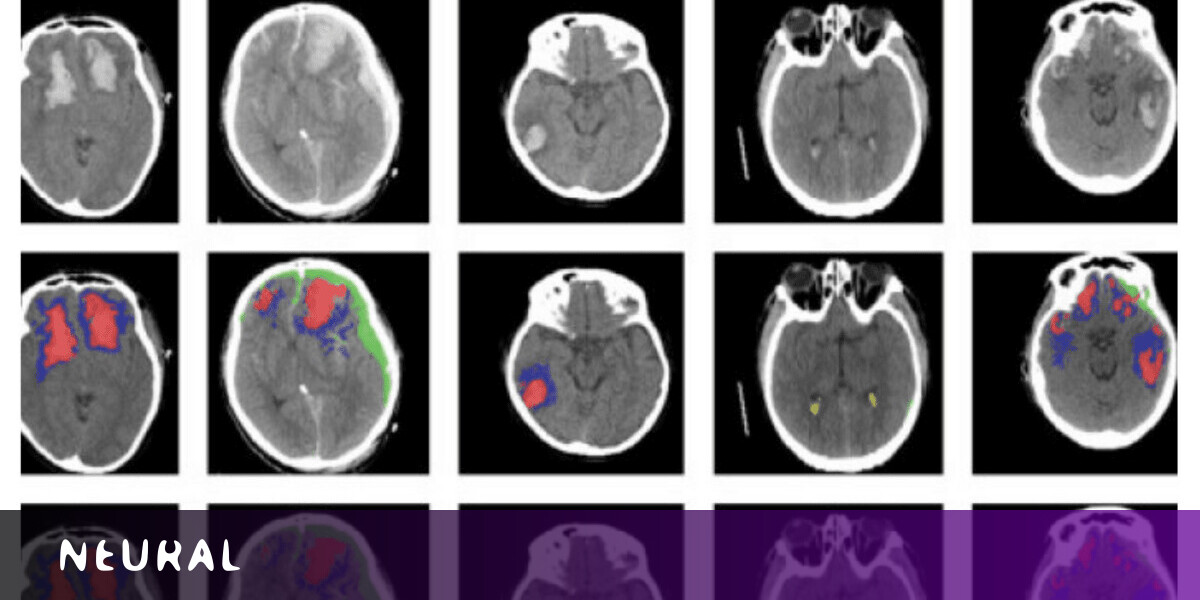

A new AI tool can automatically identify different types of brain injuries by analyzing images of CT scans.

The system uses a machine learning algorithm to detect and differentiate between types of brain lesions — areas of tissue that have been damaged through injury or disease.

The system is based on an artificial neural network developed at Imperial. The researchers trained the tool on more than 600 CT scans showing different types of brain lesions. They then checked if it worked by applying it to an existing dataset of scans.

They found that the AI successfully classified individual parts of each image — and worked out whether the brains were damaged or not.